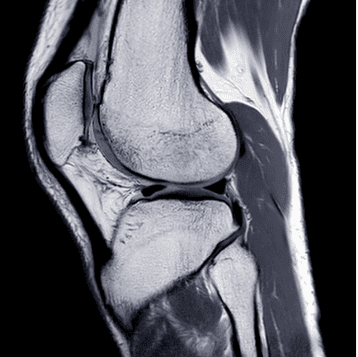

UCSF Neuro and Musculoskeletal Imaging 2022 is an online CME course providing a comprehensive update on clinically relevant neuroradiology and musculoskeletal imaging topics. It includes detailed discussions of optimized imaging protocols using 1.5T and 3T MRI to enhance image acquisition and interpretation strategies. The course content addresses indications frequently encountered in general radiology practice.

UCSF Neuro and Musculoskeletal Imaging 2022 presents up-to-date, clinically relevant knowledge in neuroradiology and musculoskeletal imaging, essential for strengthening diagnostic confidence and optimizing imaging protocols in routine practice. The content supports radiologists in refining interpretation strategies across brain, spine, head & neck, and musculoskeletal systems.